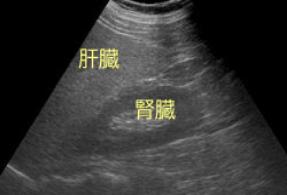

相馬医院 - 腹部エコ。

超音波検査で脂肪肝を,みて,見て,診よう 4。